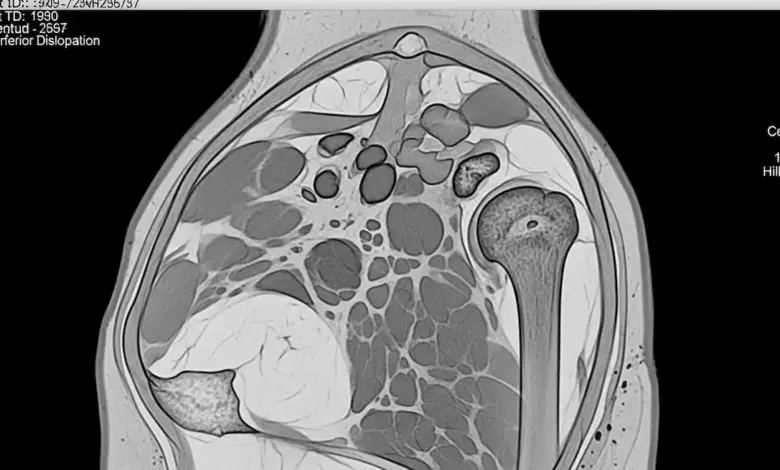

- A ressonância magnética identifica lesões labrais, capsulares e tendíneas.

- A tomografia é solicitada quando há suspeita de defeitos ósseos relevantes.

Essas informações permitem escolher a técnica adequada e prever o risco de falha do tratamento conservador.